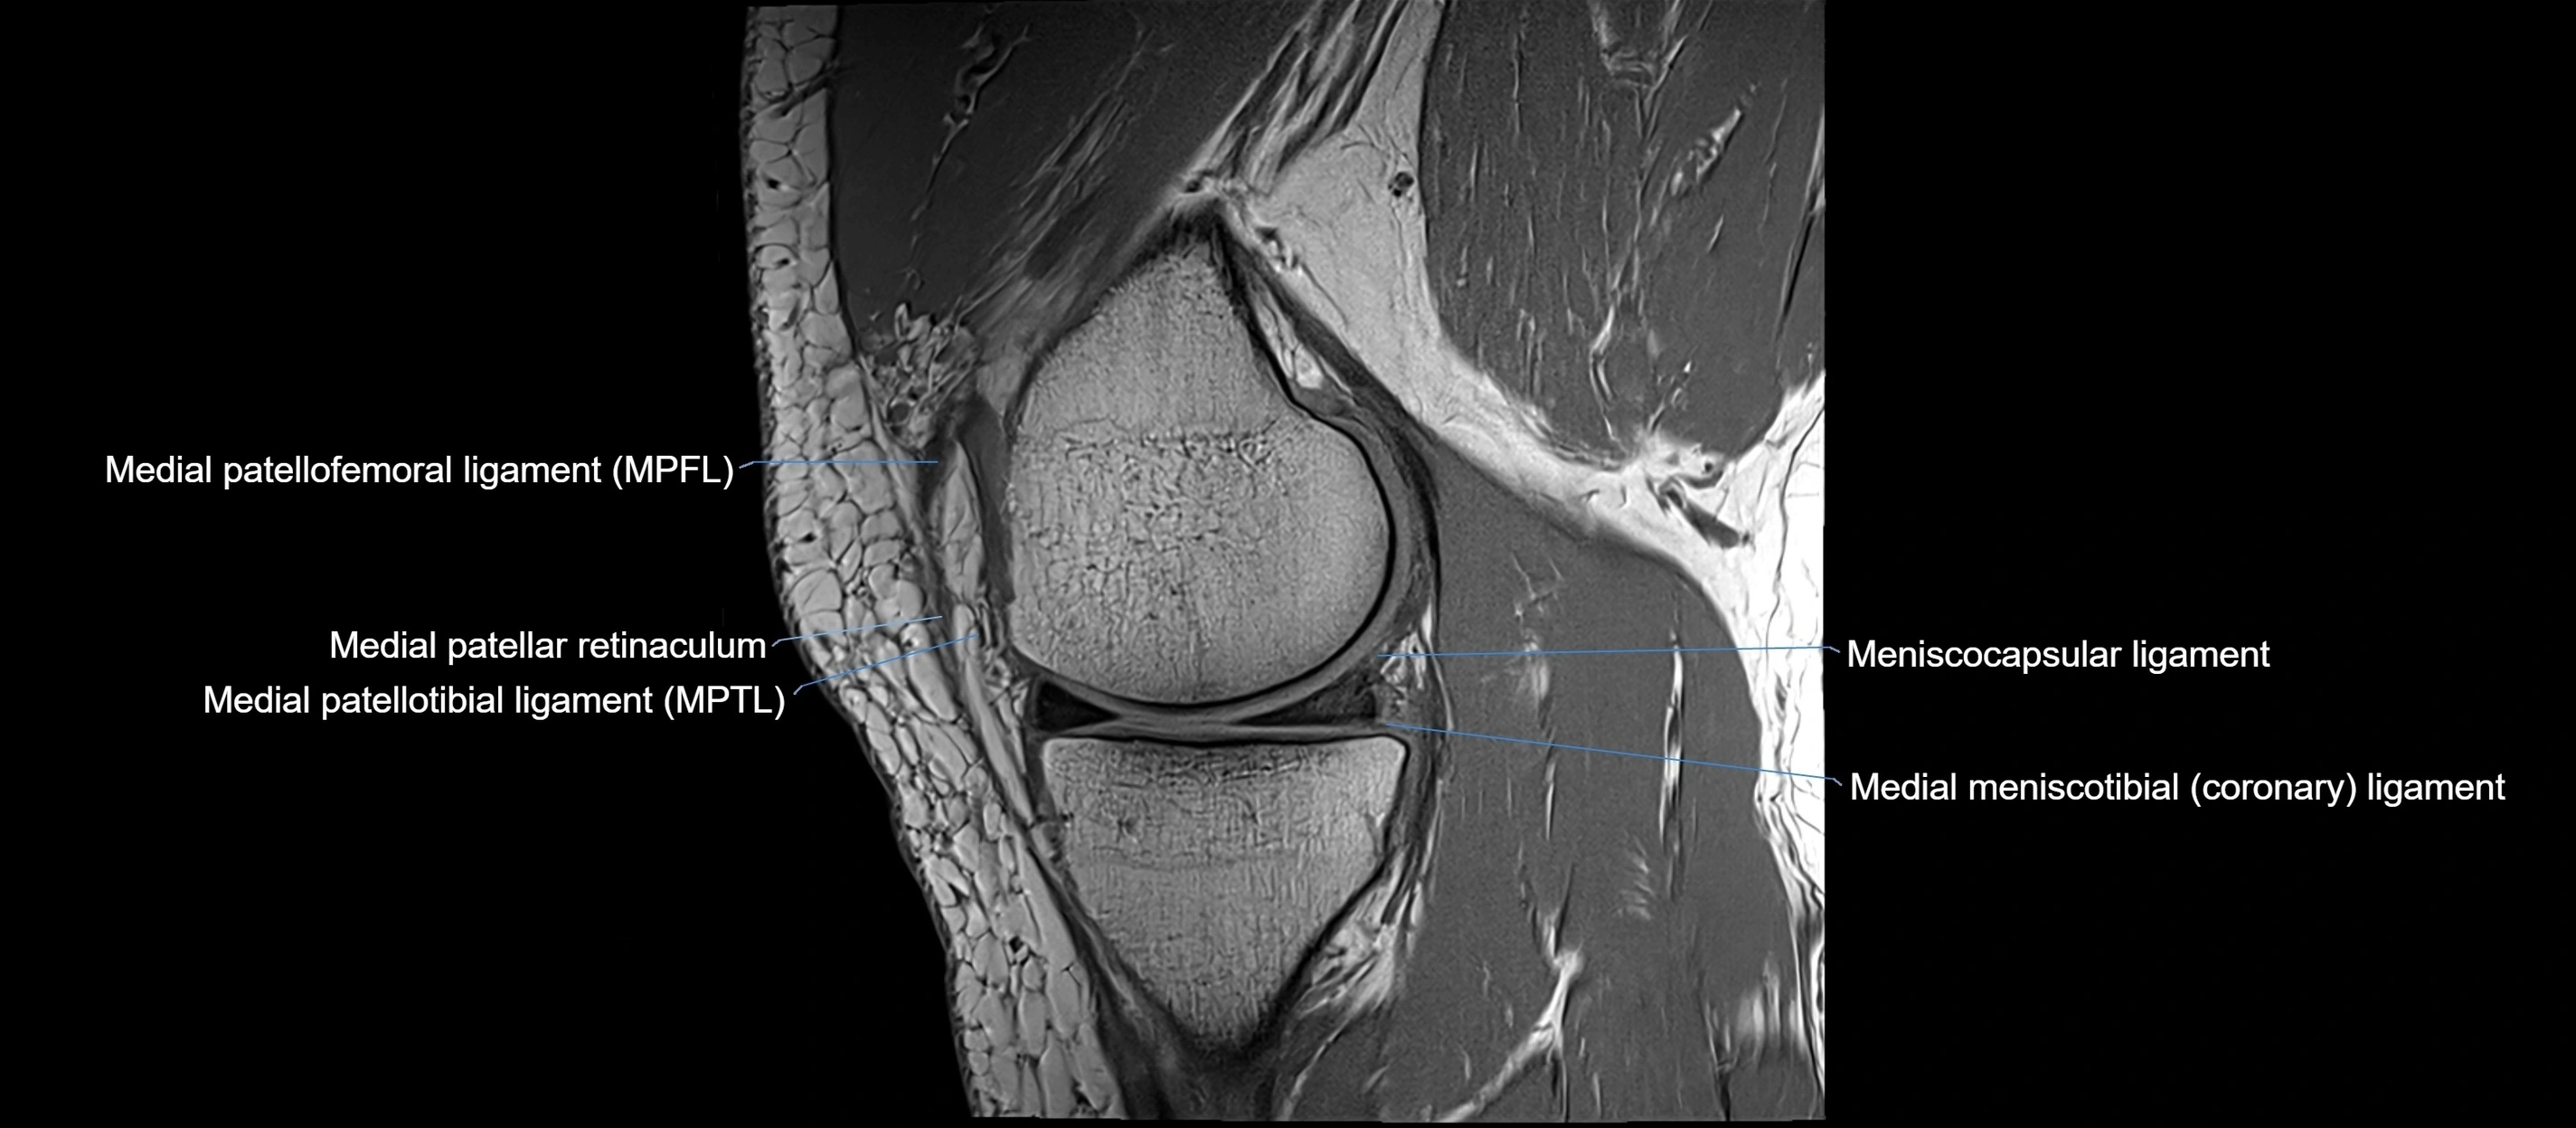

MRI Appearance

T1-weighted images:

• Normal ACL appears as a low-signal band-like structure crossing the intercondylar notch

• Surrounded by intermediate signal synovial fluid and fat planes

T2-weighted images:

• Normal ACL remains low signal

• Partial or complete tears appear as discontinuity, increased signal, or fiber laxity

MRI images

image